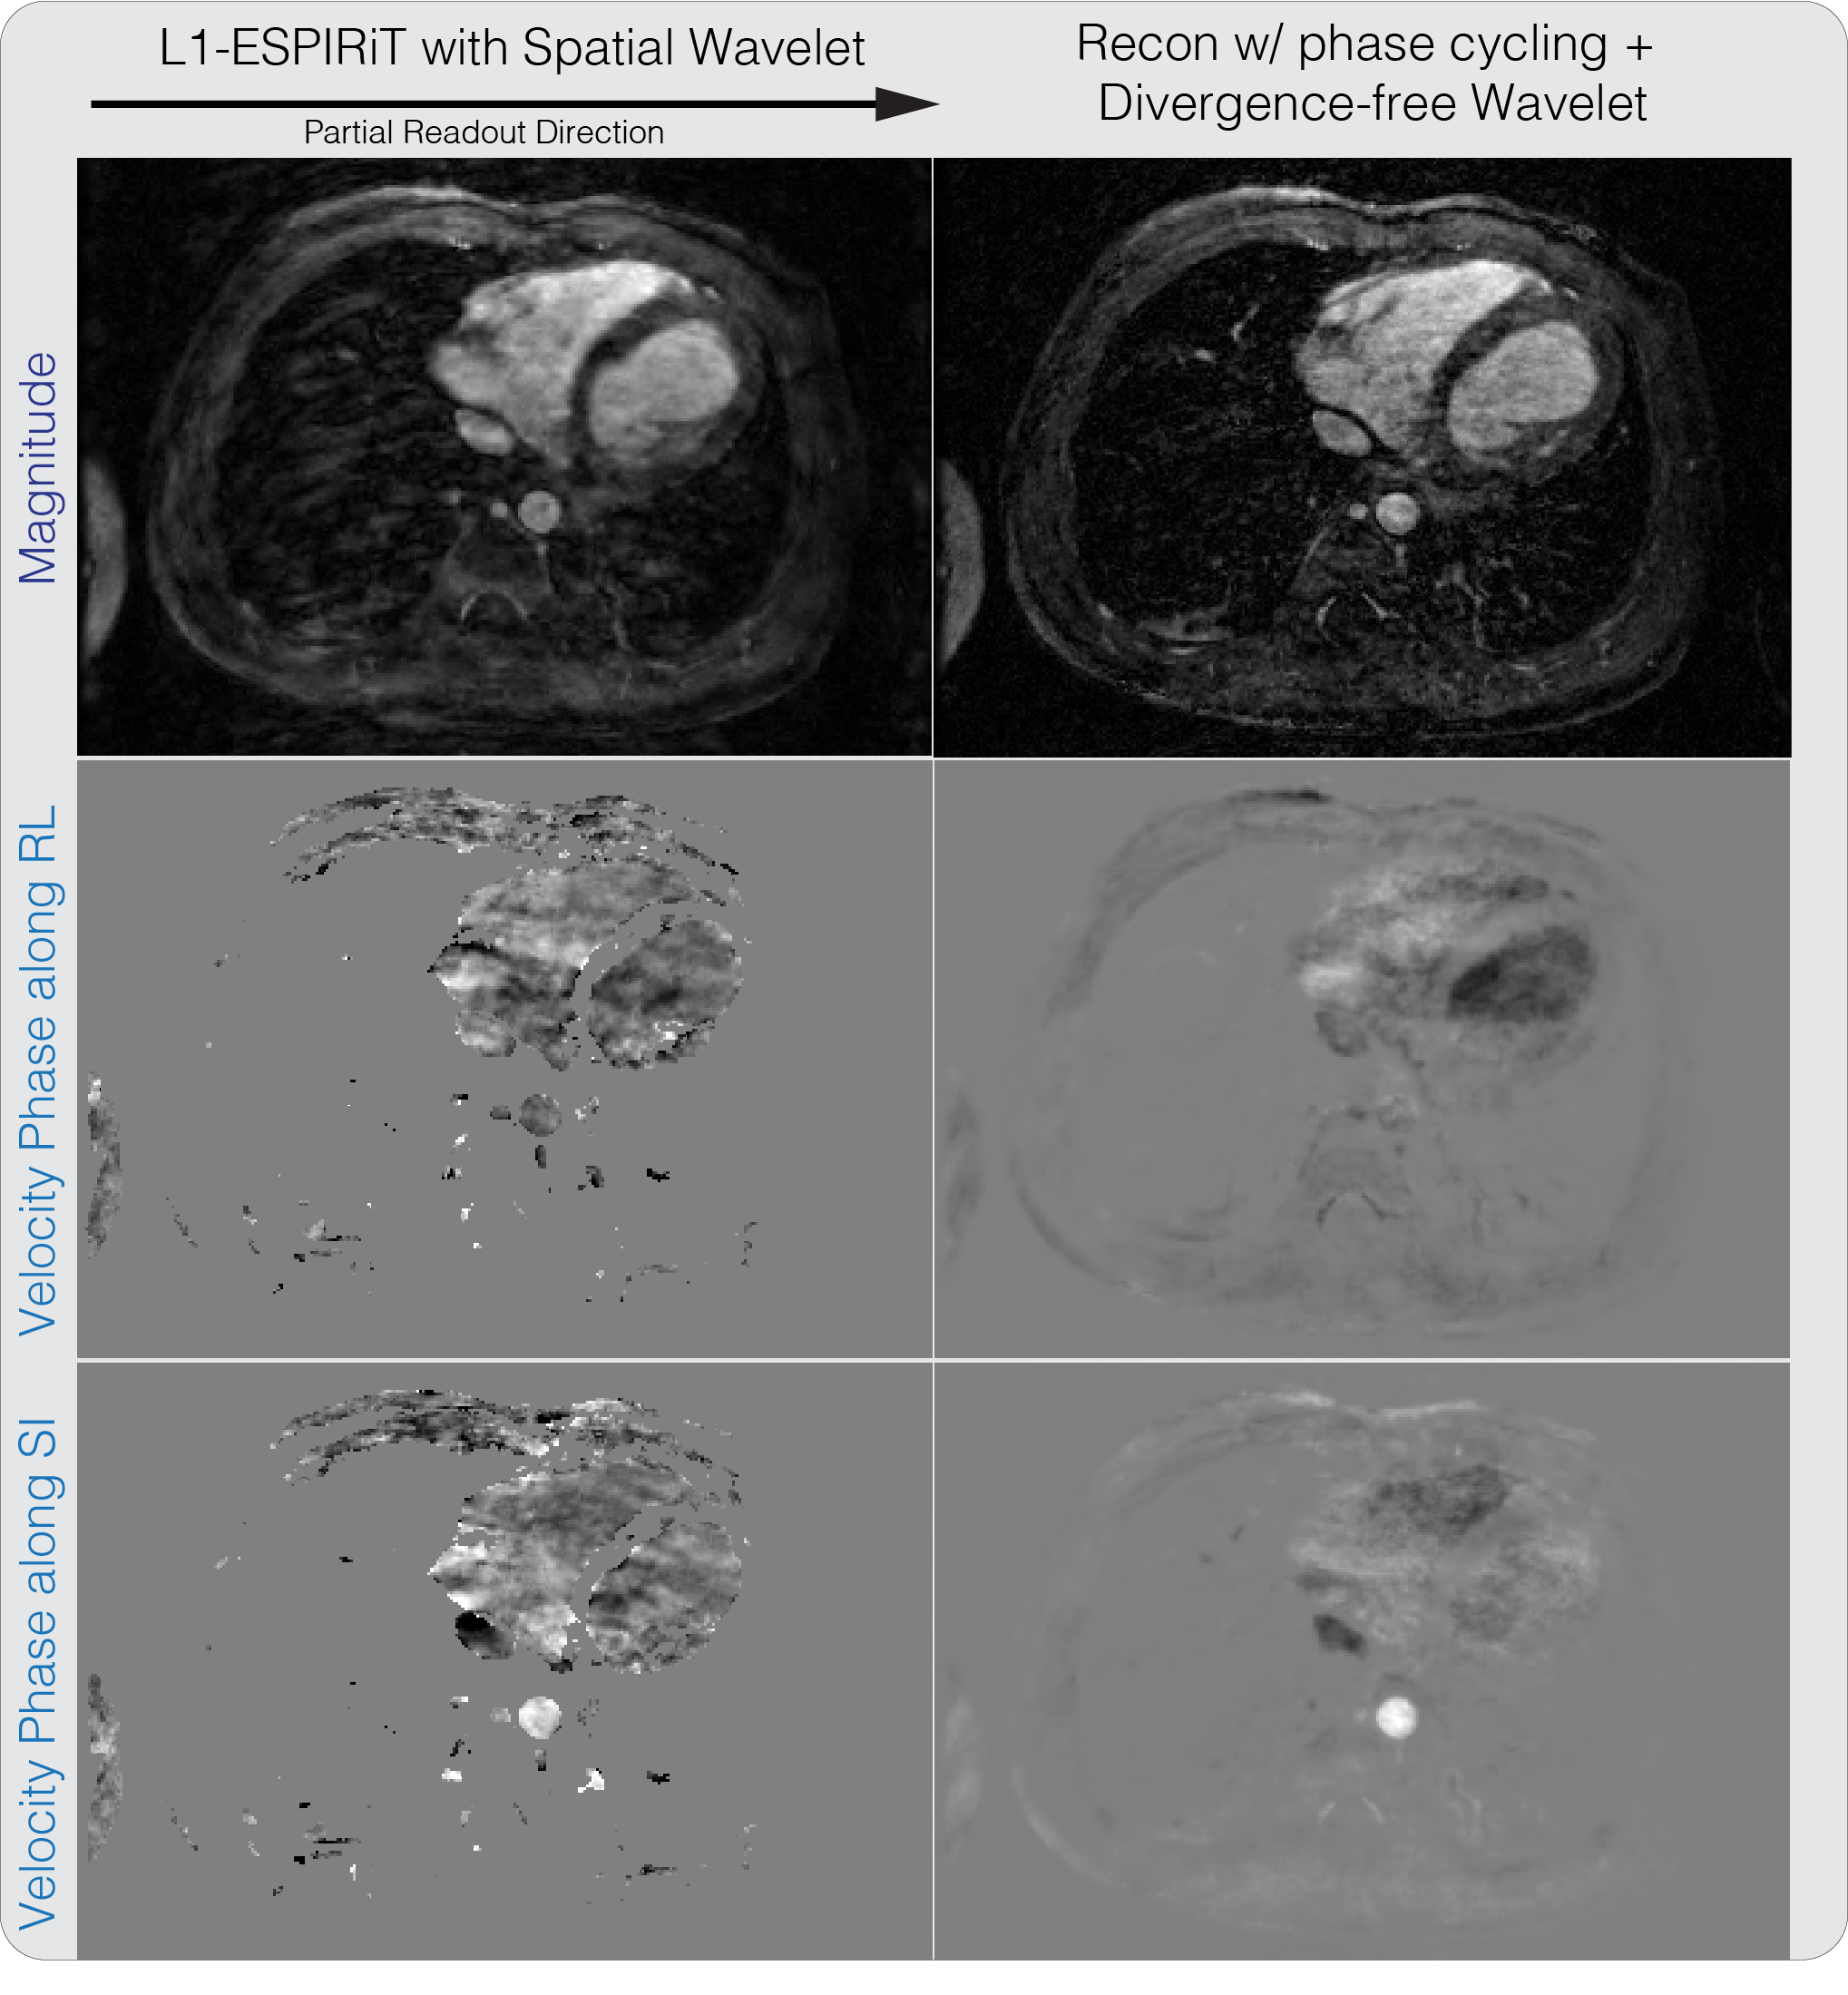

Another flow dataset of pediatric patient, with randomized flow encode undersampling using the VDRad sampling pattern [36] and a partial readout factor of 0.7, was acquired with 20 cardiac phase. The proposed method was applied and compared to -ESPIRiT.

Figure 10 shows the result of reconstructing a partial readout 4D flow dataset with randomized velocity encoding. The reconstructed magnitude image has significantly reduced blurring from partial readout, compared to the -ESPIRiT result. We also note that the velocity images are not masked and that velocities in low magnitude regions are naturally suppressed with the proposed reconstruction. One instance of our Matlab implementation of the proposed method took on the order of three hours.

Divergence-free wavelet regularized flow imaging + PI + CS reconstruction results on a 4D flow dataset. The reconstructed magnitude image has significantly reduced blurring from partial readout, compared to the -ESPIRiT result.